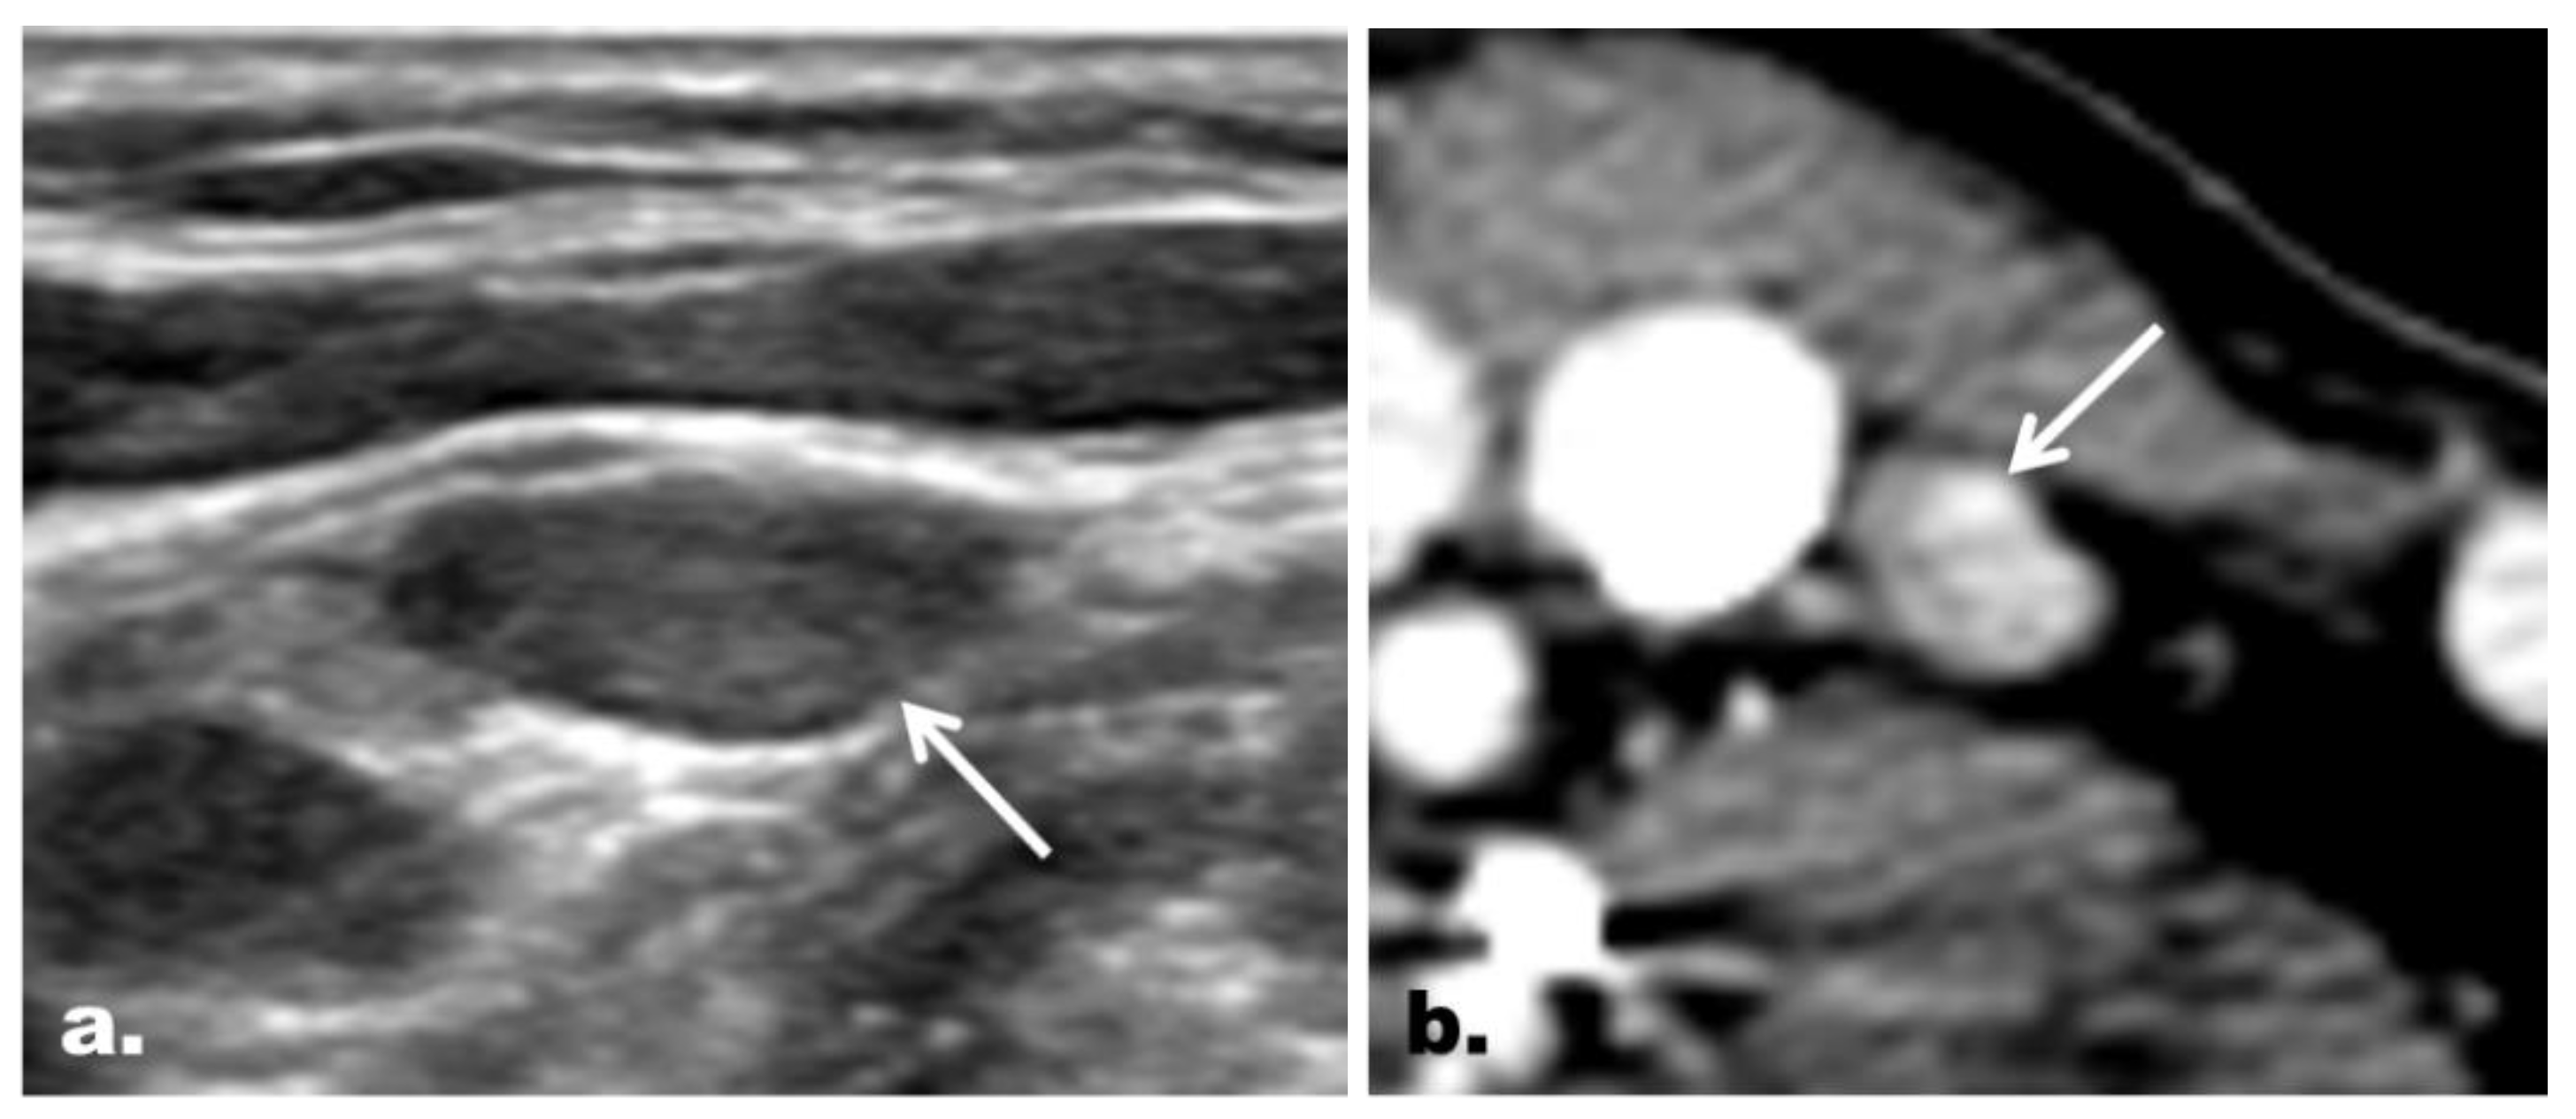

2.5. CT Imaging Features in the Reclassified Cases